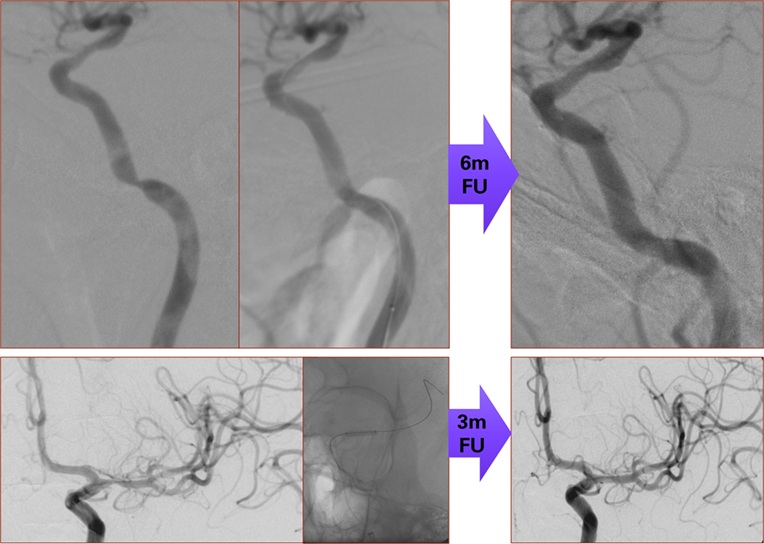

Τα N-ELUTAX “3” αποτελούν τρίτης γενιάς μπαλόνια με επικάλυψη διπλού φαρμάκου (Paclitaxel και Dextran), σχεδιασμένα για την αντιμετώπιση στενώσεων σε ενδοκρανιακές και καρωτιδικές αρτηρίες μέσω μηχανικής διάτασης και στοχευμένης φαρμακευτικής δράσης. Η μοναδική τεχνολογία τρισδιάστατης μήτρας (3D Dextran–Paclitaxel Matrix) εξασφαλίζει:

Η χρήση των ELUTAX “3” ενδείκνυται ιδιαίτερα σε περιπτώσεις:

Εγκεφαλικά αγγεία

Το μόνο εγκεκριμένο μπαλόνι DEB για χρήση σε αγγεία εγκεφάλου